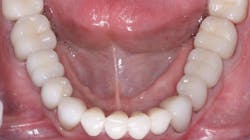

Internal staining of zirconia. Some labs are staining the 3Y, class 5 zirconia in the presintered stage, which improves the color significantly. However, this requires artistic technicians, more time, and a greater cost to the dentist (figure 3).